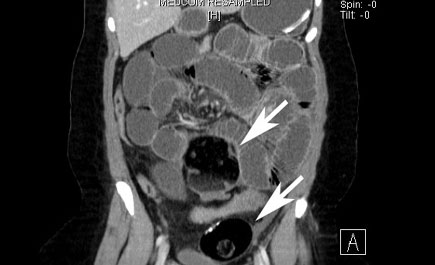

شهدت مجموعة د.سليمان الحبيب الطبية بالعليا إجراء عملية جراحية لاستئصال ورمين سرطانيين كبيرين قطر الأول 25 سم والثاني 15 سم في البطن لمريضة تبلغ من العمر 30 عاماً كانت تعاني من انسداد كامل بالأمعاء الدقيقة وآلام حادة واستفراغ وصعوبة في الإخراج لعدة أسابيع.

أوضح ذلك الدكتور ناصر الخاطر استشاري الجراحة العامة الحاصل على الزمالة البريطانية والكندية في الجراحة، وأضاف أنه بعد إجراء الفحوصات الدقيقة وإجراء الأشعة الملونة C.T. Scan للبطن تم التعرف على نوعية ومكان الورمين بدقة متناهية. ومن ثم دراسة حالة المريضة الصحية.

إثر ذلك تم اتخاذ قرار العملية الفوري لإنهاء معاناتها حيث تم إجراء عملية استكشاف للبطن (Explorotomy Laparotomy) وتم تحديد الورمين (Teratomas) وهو من النوع السرطاني الجنيني علاوة على رؤية الالتفاف الكامل للأمعاء الدقيقة حول الورمين مما أدى لانسدادها.